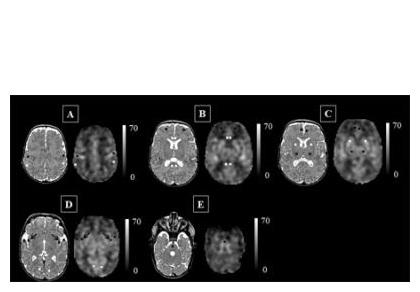

Les scientifiques aboutissent à des cartes du flux sanguin cérébral exprimé en mL / 100g / mn et montrent que, chez ces enfants, l'insula (flèches noires sur « D ») peut être particulièrement vulnérable aux stress supplémentaires de la vie. Ainsi, le flux sanguin cérébral de zones clés du cerveau peut être altéré chez les prématurés, ce qui peut constituer un signe précurseur d'une perturbation du développement cérébral bien avant que l'imagerie conventionnelle soit en mesure de la détecter.

Le débit sanguin cérébral, un bon marqueur du développement cérébral de l’enfant : ici, les chercheurs parviennent à cartographier, chez 98 nouveau-nés prématurés nés à moins de 32 semaines gestationnelles à la naissance et pesant moins de 1.500 grammes à la naissance, le débit sanguin cérébral, par imagerie par marquage de spins artériels. La technique non invasive identifie la concentration en eau du sang qui circule dans le cerveau des nourrissons afin d’identifier les zones qui reçoivent ou ne reçoivent pas le sang adéquat. Cette analyse montre que les nourrissons très prématurés présentent un débit sanguin cérébral cortical supérieur à celui des nourrissons nés à terme, mais que, dans certaines zones, dont l'insula -impliquée dans l'émotion-, le cortex cingulaire antérieur - impliqué dans les processus cognitifs- et le cortex auditif -impliqué dans le traitement du son- le débit sanguin est significativement diminué par rapport à celui de nourrissons nés à terme. Et, corrélées à ces déficiences de débit sanguin, sont identifiées des lésions cérébrales parenchymateuses.

« La maturation continue du cerveau du nouveau-né est illustrée par le schéma de distribution du flux sanguin cérébral. Grâce à cette technique d’imagerie, notre étude montre qu'en plus du tronc cérébral et de la matière grise profonde, l'insula et les zones du cerveau responsables des fonctions sensorielles et motrices sont également parmi les régions les plus oxygénées. Or, chez les nourrissons prématurés, l'insula peut être particulièrement compromise et donc vulnérable aux stress supplémentaires que l’enfant pourra rencontrer dans la vie. Ainsi, le développement altéré de l'insula et du cortex cingulaire antérieur chez ces nouveau-nés pourrait constituer les signes avant-coureurs du risque de troubles neurodéveloppementaux à long terme ».